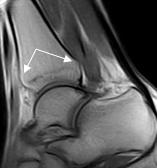

| РИС 1. Саггитальная плоскость сканирования. Т1 и Т2 ВИ. Стрелками указаны повышенное скопление жидкости в переднем и заднем заворотах, в полости суставов – большеберцово-таранном и таранно-пяточном. |

При МР-томографии интенсивность сигнала задней малоберцово-таранной связки повышена на Т2 ВИ, контуры прерывисты.

| Рис 3. Саггитальная плоскость сканирования. Т2 и Т1 ВИ. Стрелками указаны повышенное скопление жидкости в переднем и заднем заворотах, в полости суставов – большеберцово-таранном и таранно-пяточном. Повреждение каких-либо связок можно лишь предположить. |